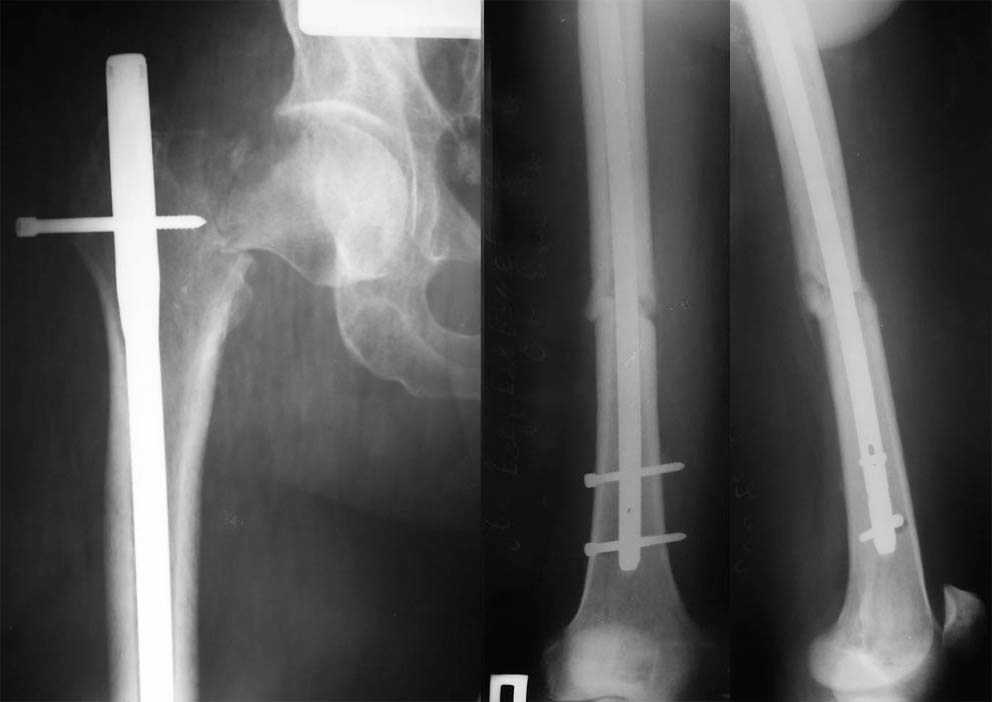

This is very bad situation. To miss fracture subcapital like this is unforgivable. Now the fracture of the femoral shaft isn't healed with malreduction component and fracture of the subcapital femur (doesn't matter what grade) without any chance for healing. More of them, therк is very high chanse to AVN of the femoral head. At the moment nothing can be done exept change of the intramedullary nail in femoral shaft

with femoral neck fixation after open reduction . I mean PF Aesculap nail or TAN Smith & Nerphuy). After that waiting with hoope to union of the femoral shaft fracture and, depending on condition of the femoral head, in the life - suprise, or go to THR noncemented if the head will be dead. Any way this young man is invalid. Good luck !

I was sure that you can read in english.At the moment nothing can be done exept change of the intramedullary nail in femoral shaft.Nail with femoral neck fixation after open reduction. This may be PF Aesculap nail or TAN Smith & Nerphuy

Уважаемые коллеги. Благодарим за дискуссию. Мы решили выполнить комбинированную операцию - эндопротезирование тазобедренного сустава и ретроградный интрамедуллярный остеосинтез (одномоментно)